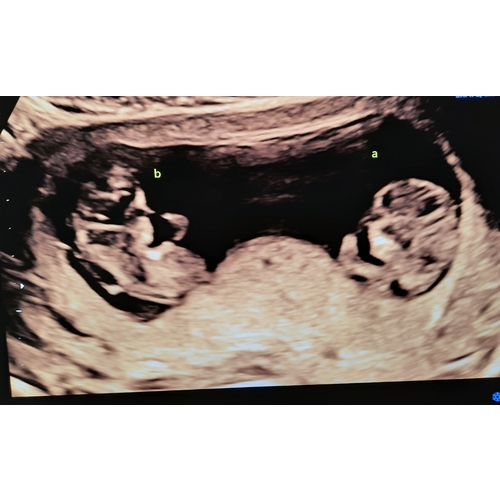

Wij zijn voor de eerste keer in verwachting 鈾ワ笍 na jarenlang proberen en vruchtbaarheidsbehandelingen kregen wij 2 weken geleden het nieuws in verwachting te zijn van een eeneiige tweeling. Zo niet verwacht maar zo welkom 馃グ

Wij hebben vandaag een echo gehad met 10+3 weken. En toch een verrassing: het is een eeneiige tweeling. Ze waren gelukkig even groot en lekker beweegelijk. Vanaf nu elke twee weken een echo.